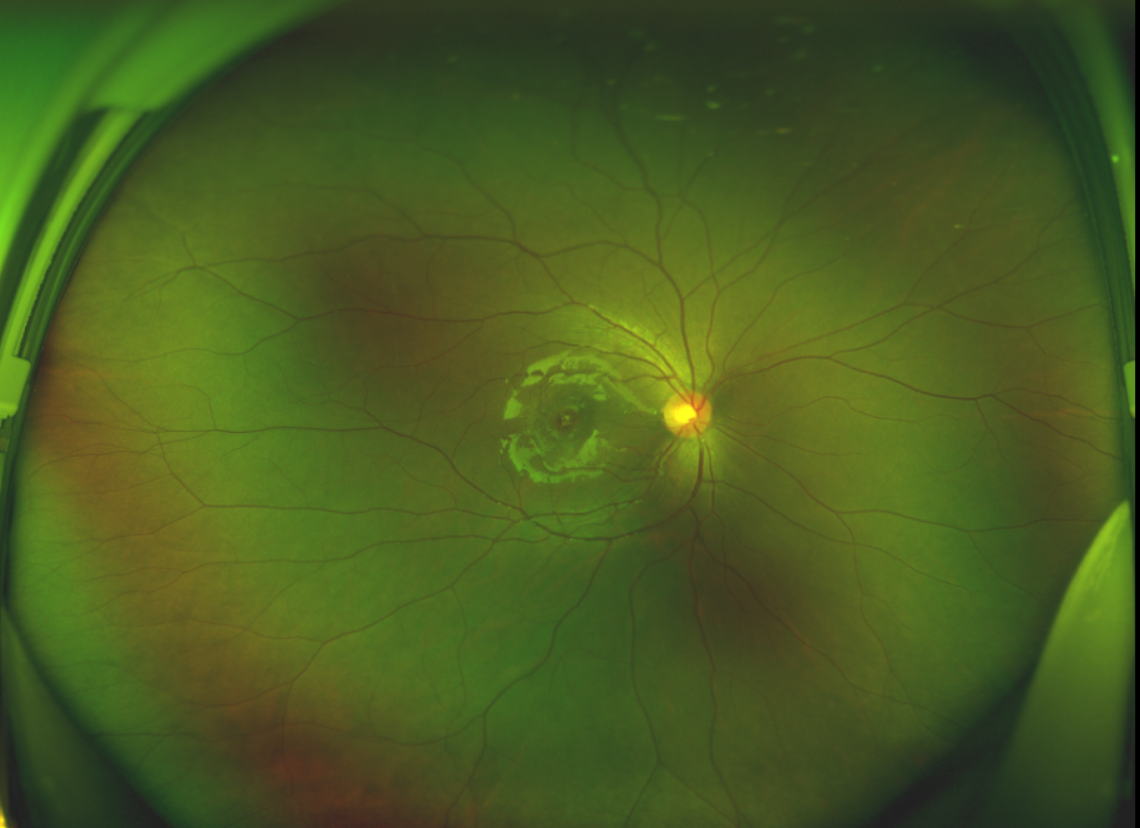

半年前的一次意外,誠誠(化名)右眼不慎受傷導(dǎo)致黃斑裂孔。從此,他的“視”界不再清晰,也不再有直線條……

黃斑位于視網(wǎng)膜正中心,是視覺最敏銳的區(qū)域,堪稱“眼底的心臟”,負責我們閱讀、駕駛、識別人臉等精細視覺。 當黃斑區(qū)的神經(jīng)組織出現(xiàn)全層缺損,形成一個“孔洞”,即為黃斑裂孔,它會直接導(dǎo)致中心視力急劇下降、視物變形、視野中心出現(xiàn)暗區(qū)。

除此之外,利用自體組織覆蓋為黃斑裂孔提供了理想的愈合環(huán)境,裂孔閉合速度顯著快于傳統(tǒng)方法。誠誠接受手術(shù)24小時后,檢查可見內(nèi)界膜瓣位置良好;術(shù)后1個月,黃斑裂孔已經(jīng)閉合,視力恢復(fù)到0.5;術(shù)后兩個月,視力進一步提升到0.7。